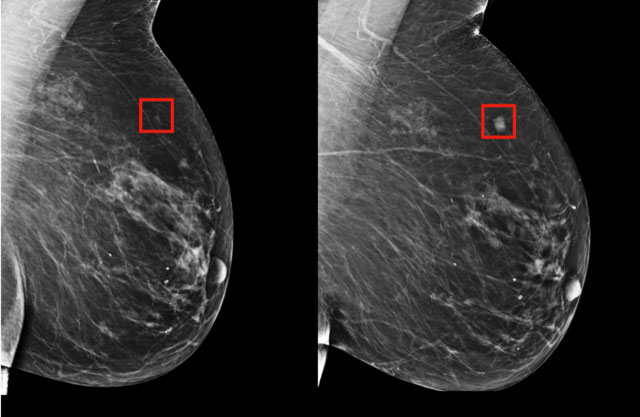

H ΔΕΛΤΑ ΨΗΦΙΑΚΗ με πρωταρχικό στόχο την παροχή υπηρεσιών υψηλού επιστημονικού και τεχνολογικού επιπέδου στις ασθενείς της , μετά την εγκατάσταση του συστήματος ΤΕΧΝΗΤΗΣ ΝΟΗΜΟΣΥΝΗΣ (Deep Learning) Profound ΑΙ - 3D στην Ψηφιακή Τομοσύνθεση Μαστού, εγκατέστησε σύστημα ΤΕΧΝΗΤΗΣ ΝΟΗΜΟΣΥΝΗΣ (ΑΙ Deep Learning) PROFOUND και στην ΨΗΦΙΑΚΗ ΜΑΣΤΟΓΡΑΦΙΑ . Το σύστημα είναι εξαιρετικά υψηλής τεχνολογίας, της Aμερικανικής εταιρείας iCAD. Eίναι το πρώτο σύστημα Τεχνητής Νοημοσύνης στην 2D ΨΗΦΙΑΚΗ ΜΑΣΤΟΓΡΑΦΙΑ που εγκαθίσταται στην Ελλάδα. Το σύστημα χρησιμοποιεί τεχνολογία ΑΙ Deep Learning, είναι εκπαιδευμένο με 10000 περιστατικά καρκίνου μαστού και 10000 φυσιολογικά περιστατικά. Είναι προγραμματισμένο να αναγνωρίζει μόνο του και να αξιολογεί ογκόμορφες βλάβες, διαταραχές αρχιτεκτονικής και αποτιτανώσεις, με πολύ υψηλή αξιοπιστία. Λειτουργεί ως ένας επιπλέον γιατρός , έχοντας καλύτερες επιδόσεις ακόμη και από τους πλέον έμπειρους Ακτινολόγους. Εστιάζει την προσοχή του ιατρού ακόμη και σε πολύ μικρές βλάβες και σε πυκνούς και δύσκολους μαστούς, που θα μπορούσαν να διαφύγουν και να καθυστερήσει η διάγνωση. Έχει ευαισθησία 93% και ειδικότητα 85%. Το σύστημα περιγράφει τις βλάβες και αξιολογεί την πιθανότητα ύπαρξης κακοήθειας, συγκρίνοντας την βλάβη με την βάση δεδομένων του. Παρέχει στον ιατρό το lesion score που αφορά την συγκεκριμένη βλάβη και ένα case score που αφορά την πιθανότητα κακοήθειας του περιστατικού συνυπολογίζοντας την πυκνότητα των μαστών και την πιθανή ύπαρξη και άλλων βλαβών. Λειτουργώντας συνεργατικά με τον γιατρό, ανεβάζει την ευαισθησία και την ειδικότητα της ΨΗΦΙΑΚΗΣ ΜΑΣΤΟΓΡΑΦΙΑΣ κατά 10%, επιτυγχάνοντας εξαιρετικά αποτελέσματα. Το σύστημα εκπαιδεύεται συνεχώς με νέα περιστατικά και υφίσταται συνεχείς αναβαθμίσεις με στόχο την απόλυτη τελειότητα. Επεξεργάζεται ταχύτατα τα δεδομένα των εξετάσεων, παράλληλα με την αξιολόγηση της εξέτασης από τον ιατρό, μειώνοντας το χρόνο διάγνωσης , ελαχιστοποιώντας την κόπωση των γιατρών και εξοικονομώντας χρόνο προς όφελος της διαγνωστικής ακρίβειας και της ενασχόλησης με τις ασθενείς.